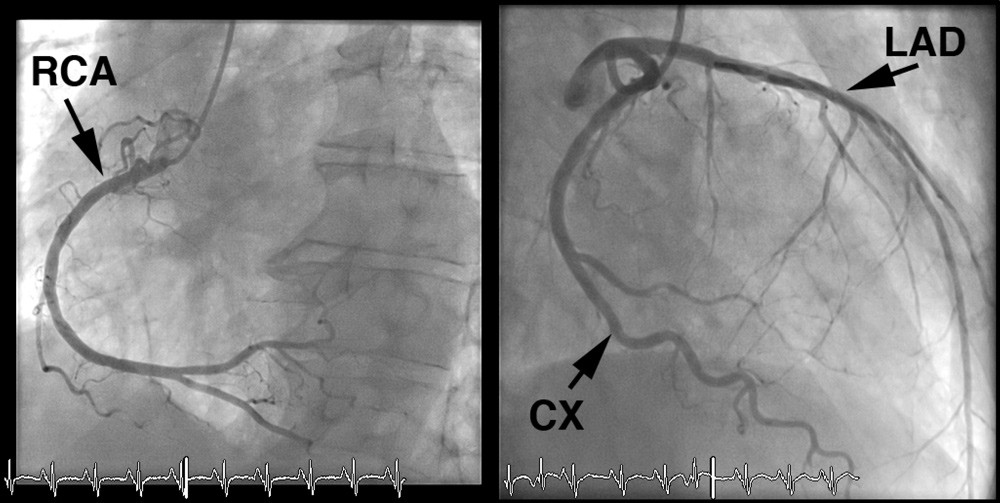

Pasienten hadde lav risikoprofil for koronarsykdom – han var til vanlig fysisk aktiv, var ikke-røyker, hadde ikke kjent diabetes, hypertensjon eller hyperkolesterolemi, og det var ingen familiær belastning for koronarsykdom. Koronar angiografi utført dagen etter overflyttingen viste mindre veggforandringer, men ingen signifikante stenoser (≥ 50 % reduksjon i karlumendiameter) i koronarkarene (fig 2).

Pasienten hadde utviklet en alvorlig hjertesvikt med symptomer i hvile – New York Heart Association (NYHA) klasse IV. Det var beskjedne funn ved koronar angiografi, og de kunne ikke forklare den betydelige reduksjonen i venstre ventrikkels funksjon. De regionale forskjellene i kontraktilitet passet heller ikke med takotsubokardiomyopati. EKG med ST-T-forandringer og høyt troponin I-nivå gjorde at man nå mistenkte myokarditt. Ticagrelor ble seponert, mens pasienten fortsatt fikk acetylsalisylsyre og statin på grunn av påviste veggforandringer i koronararteriene.

Ved brystsmerter og forhøyede troponinverdier er det først og fremst mistanke om akutt koronarsyndrom med hjerteinfarkt. Disse pasientene skal vanligvis henvises til koronar angiografi. Ved funn av normale koronarkar eller ved beskjedne koronare forandringer, som hos vår pasient, må annen årsak til troponinstigning vurderes.